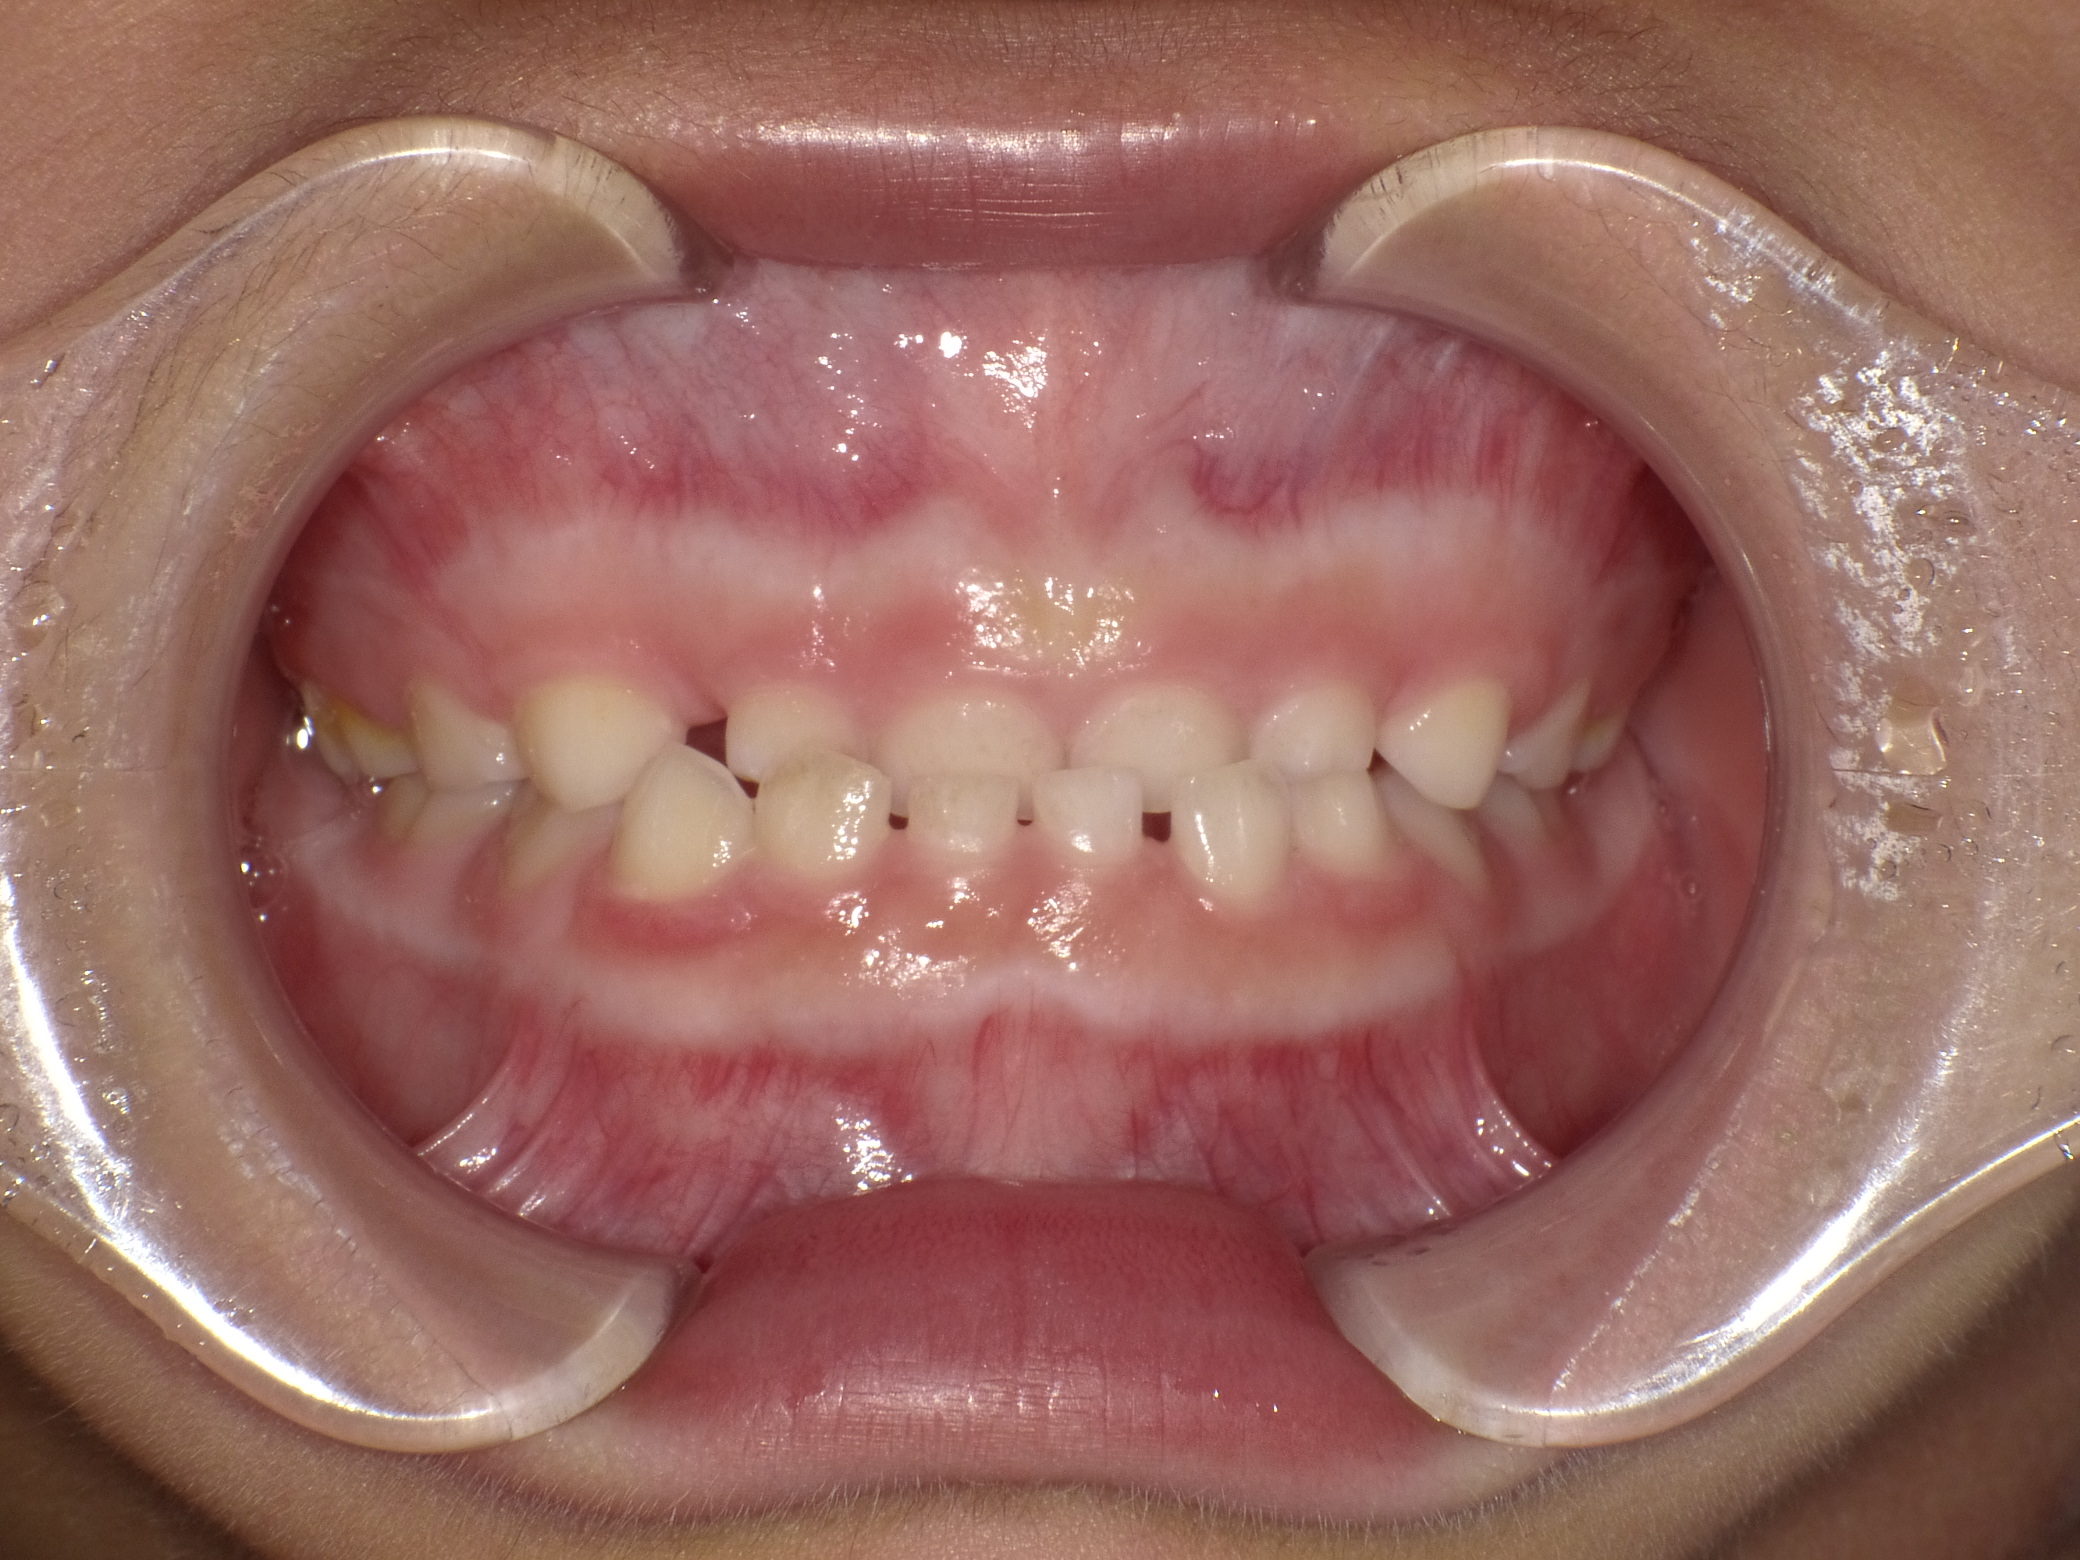

治療後

治療方法:

上下左右の第1小臼歯(4番)を抜歯し、マウスピース型矯正装置を用いて歯並びとかみ合わせの改善を行いました

治療期間:

2年

治療のポイント:

・抜歯によりスペースを確保し、前歯の位置と角度をコントロール

・マウスピース矯正により、見た目と快適さに配慮しながら治療

・奥歯の高さを調整し、前歯がしっかり噛むように改善

・舌のクセ(舌突出癖)にも配慮し、後戻りを予防